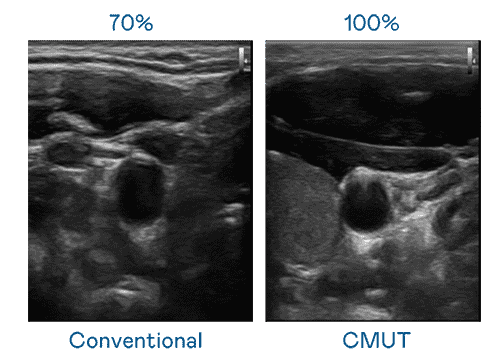

CMUT 技术是一种用电容式微机电元件来产生超音波讯号的技术。。与传统 PZT 压电式技术相比,,,CMUT 频宽增加 30%,,,,更宽频的超音波讯号让影像解析度大幅提升,,,是实现高影像品质医疗超音波扫描、、、、促进精准医疗发展的关键技术。。

大频宽带来超清晰影像

超音波影像的解析度高低,,首先取决于探头能发出的讯号频宽。。。。z6mg·人生就是博 CMUT 可提供高清晰的超音波讯号,,,,提供高频宽、、、、高灵敏度、、影像纹理细节更高的超音波影像,,,协助医护人员缩短影像判读时间及利用精准的医疗影像进行诊断。。。。